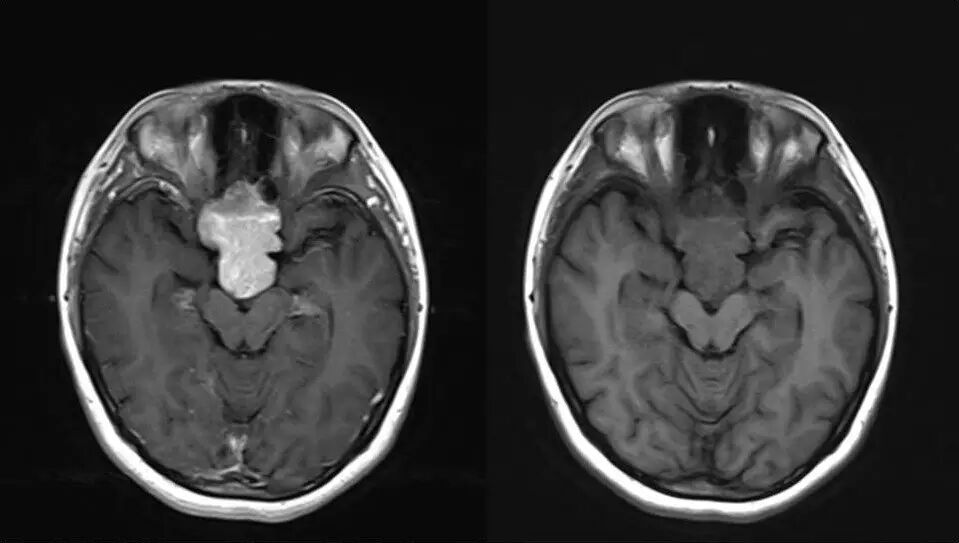

影像资料

2.MR检查显示肿瘤位于鞍区,分叶状生长,呈稍长T2、稍长T1异常信号影,边界清楚,内部信号不均匀,其内可见“微囊”状异常信号影,视交叉受压上抬,DWI呈等或略高信号影,注药后呈不均匀明显强化;

3.CT检查显示肿瘤呈等密度影,可见鞍背骨质破坏;

4.重点观察冠状位:病变源于垂体偏左侧,与垂体界限不清楚,肿瘤偏右侧可见垂体与肿瘤之间裂隙,造成矢状位平扫及强化后误认为正常垂体存在,从而首先除外了垂体瘤,导致误诊;

5.影像表现确定肿瘤源于垂体,部位、信号、生长方式、内部结构、骨质破坏,增强显示等均符合垂体瘤诊断。